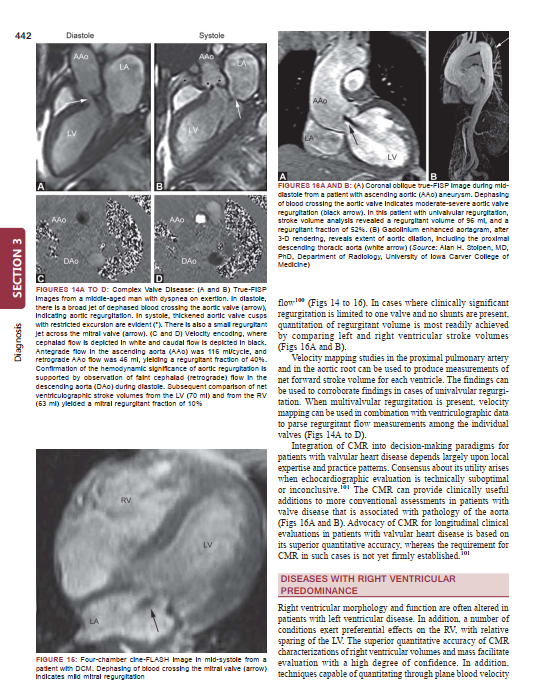

Description